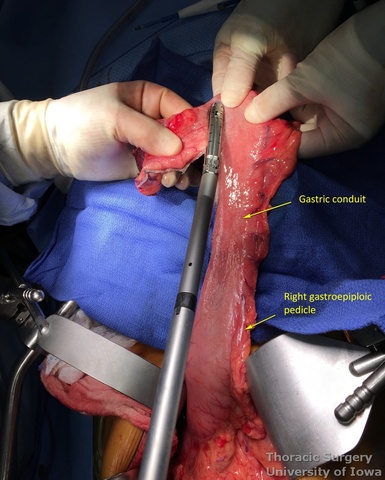

- Starting from the lesser curvature of the stomach, several stapler loads are sequentially fired towards the fundus of the stomach, thus creating a 4–5 cm wide gastric conduit and ensuring a 5 cm margin distal to the tumor. Depending on the thickness of the stomach, medium purple or thick black (alternatively blue or green, depending on manufacturer) loads are used.

- Gastric conduit should reach the cervical incision.

- The gastric conduit stapler line is then oversewn with a running 4-0 (KP and JK) or 3-0 (EA) PDS.

- A Saratoga sump drain (or chest tube) is advanced from the cervical incision through the chest into the abdomen. A Penrose drain is sewn to the anterior wall of the gastric tube (in the area of expected gastrotomy for the anastomosis) and tied over the sump drain.

- The gastric conduit is gently delivered through the mediastinum into the neck without torsion.